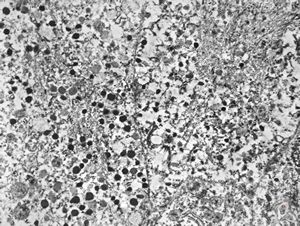

F,41y. | synovial metaplasia - capsule of implantate

F,41y. | synovial metaplasia - capsule of implantate

F,41y. | synovial metaplasia - capsule of implantate

F,41y. | synovial metaplasia - capsule of implantate

F,41y. | synovial metaplasia - capsule of implantate

F,41y. | synovial metaplasia - capsule of implantate

F,41y. | synovial metaplasia - capsule of implantate

F,41y. | synovial metaplasia - capsule of implantate

F,41y. | synovial metaplasia - capsule of implantate